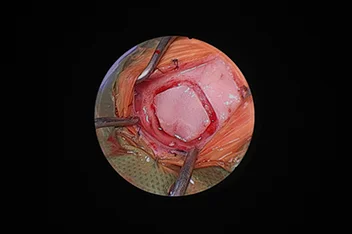

환축추아탈구(AAI)

AAI stabilization(screw + PMMA)

• AAI